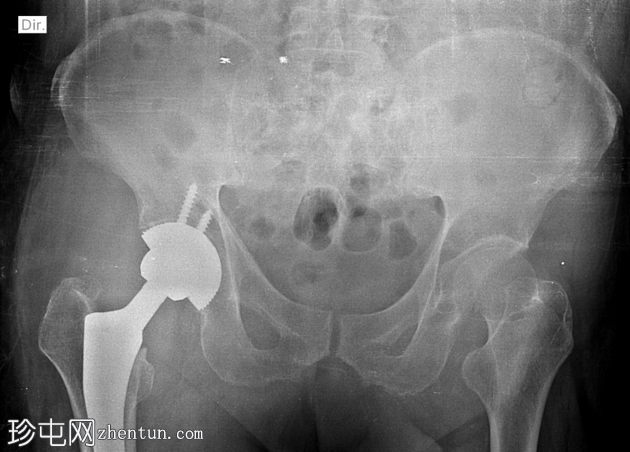

X线片

1.png

右髋关节非骨水泥全髋关节置换术后假体后脱位。

未见假体周围骨折或假体松动。